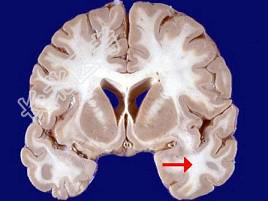

- 单项选择题如图箭头所示为大脑哪个部位 ( )

A、额叶

B、颞叶

C、枕叶

D、顶叶

E、岛叶